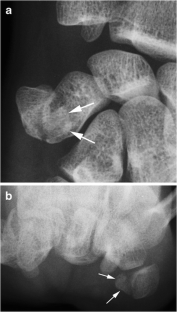

Fig. 2